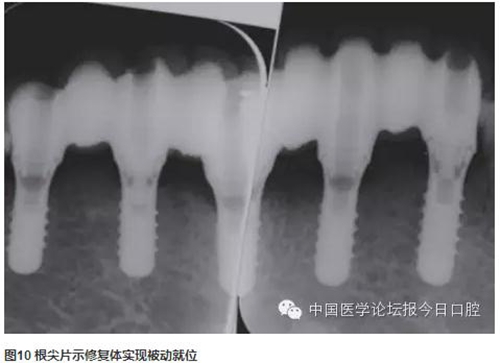

技工室制作純鈦支架,聚合瓷修復(fù)牙齒和牙齦形態(tài),患者口內(nèi)試戴,只將一個(gè)種植體的固定螺絲加力,拍片可見(jiàn)其余3顆種植體均實(shí)現(xiàn)被動(dòng)就位,然后將4顆種植體固定螺絲加力,封口(圖2~圖10)。

CAD/CAM螺絲固位固定修復(fù)體就位順利,咬合關(guān)系正常,牙齒與牙齦顏色患者較滿意。

曲面體層片示:種植體基臺(tái)與修復(fù)體密合性良好。1年后復(fù)診,支架無(wú)松動(dòng)、折斷,中央螺絲未見(jiàn)折斷、松動(dòng),修復(fù)體未見(jiàn)崩瓷。種植體無(wú)松動(dòng),種植體周?chē)倭寇浌复妫つの匆?jiàn)紅腫。種植體周?chē)皆\深度:下頜左側(cè)尖牙(近中2mm、頰側(cè)3mm、遠(yuǎn)中4mm、舌側(cè)2mm),下頜左側(cè)中切牙(近中2mm、頰側(cè)2mm、遠(yuǎn)中4mm、舌側(cè)2mm),下頜右側(cè)側(cè)切牙(近中2mm、頰側(cè)2mm、遠(yuǎn)中3mm、舌側(cè)3mm),下頜右側(cè)第一前磨牙(近中3mm、頰側(cè)2mm、遠(yuǎn)中4mm、舌側(cè)3mm)(圖11~圖13)。